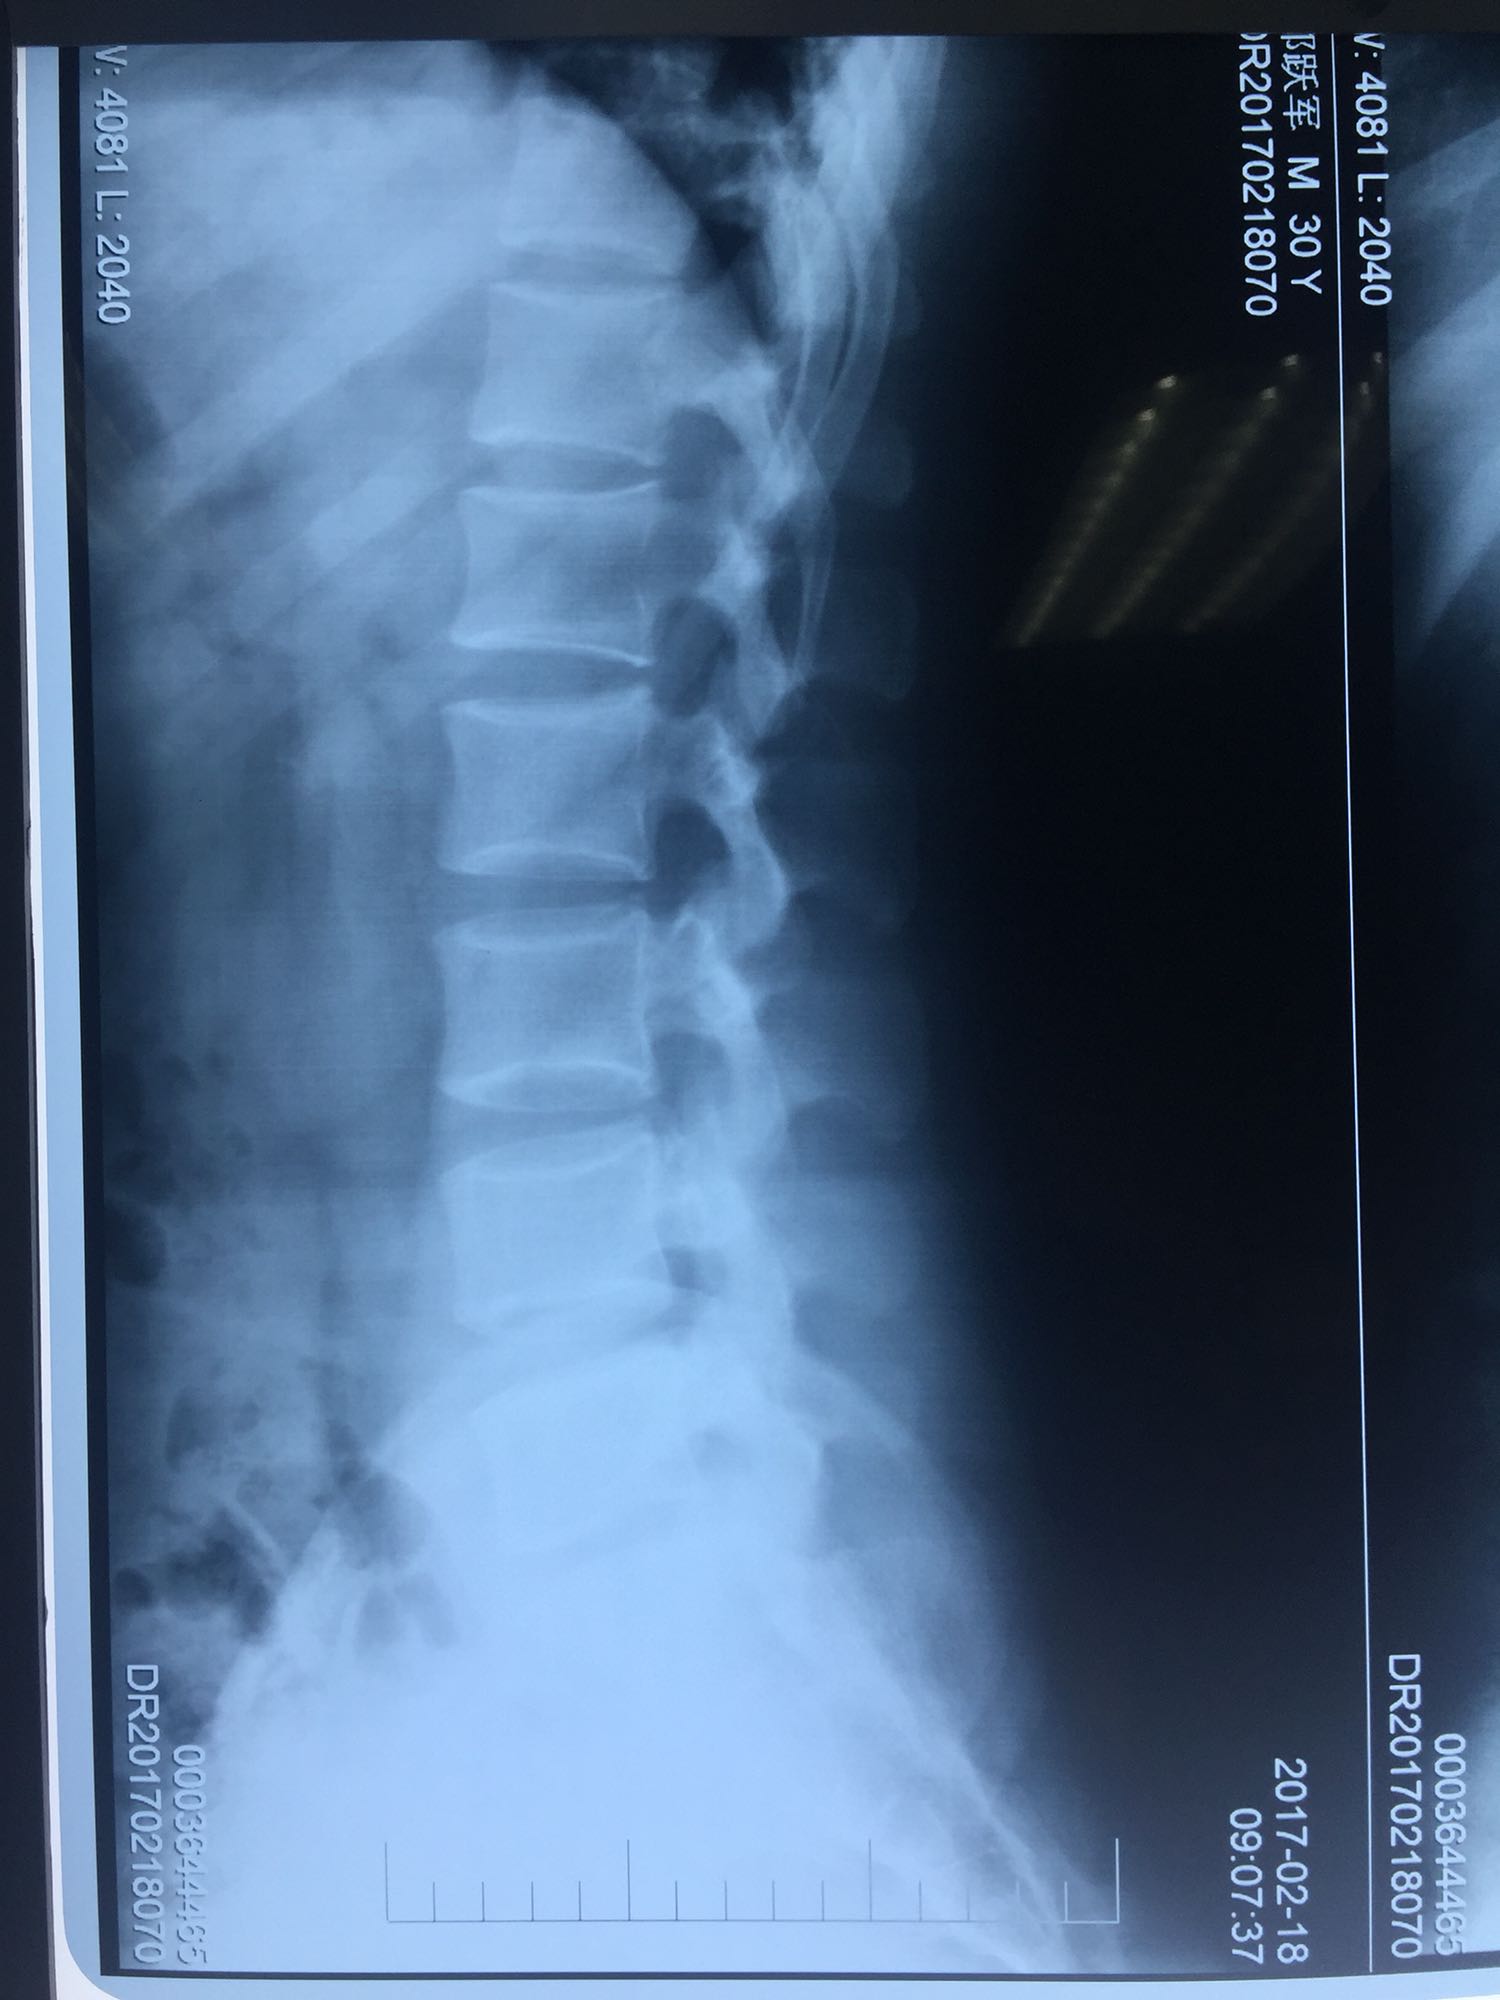

椎间孔镜下腰5骶1椎板间隙入路髓核摘除术

腰椎间盘脱出

腰骶部肌紧张,腰5骶1棘间及左侧椎旁有压痛及放散痛,左侧坐骨神经出孔处有压痛及放散痛,左侧足背外侧及足底部皮肤感觉麻木,左侧直腿抬高试验阳性(30度)。

诊断:腰5骶1椎间盘突出症 治疗方案:椎间孔镜下经椎板间入路髓核摘除术